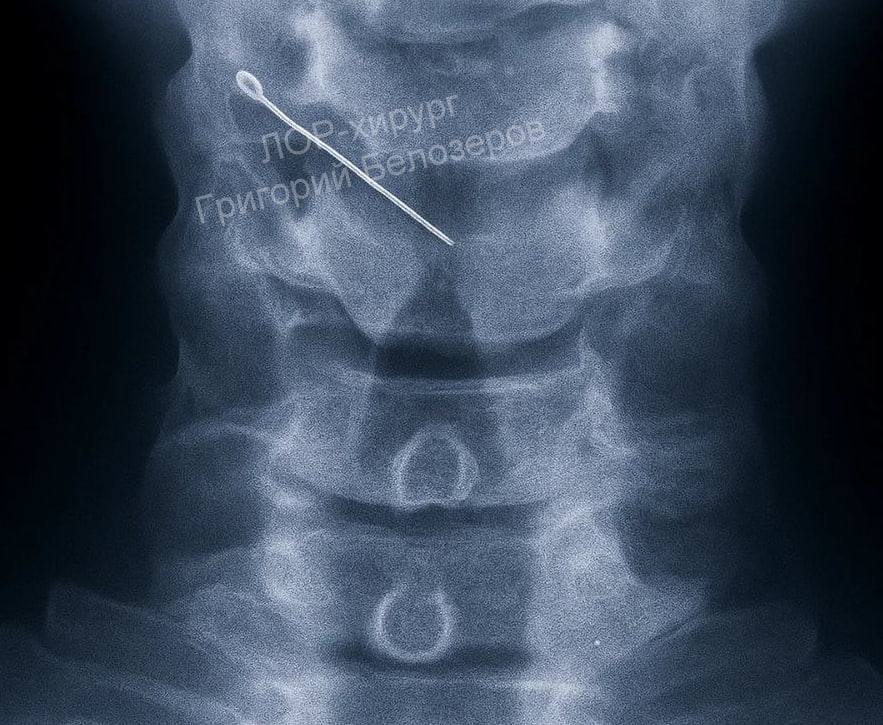

Иголка застряла в горле у жителя Нижнего Новгорода.

По словам ЛОР-хирурга Георгия Белозерова, сначала она попала в мягкие ткани, а после дошла до крупных мышц. Благо, ее удалось вытащить.